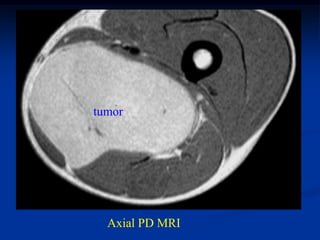

Case #1186

51 year male with

intramuscular lipoma

posterior compartment

thigh

Axial T-1 MRI

Case #1186 51 yearmale with intramuscular lipoma posterior compartment thigh

• 58.

• 59.